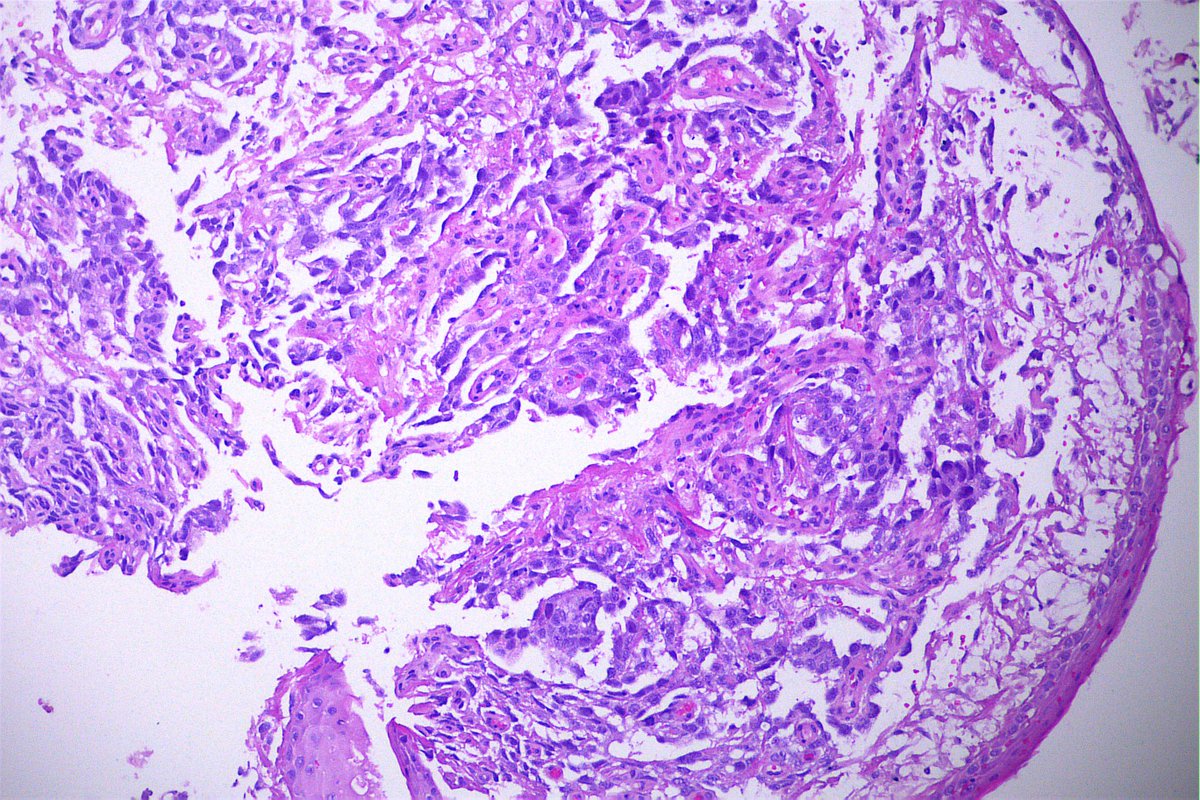

Case of the day. M, 30 years old, with weight loss, pulmonary consolidation area, mediastinal lymph node enlargement, and endobronchial polypoid lesions. Bronchial biopsy performed. #pulmpath #pathology